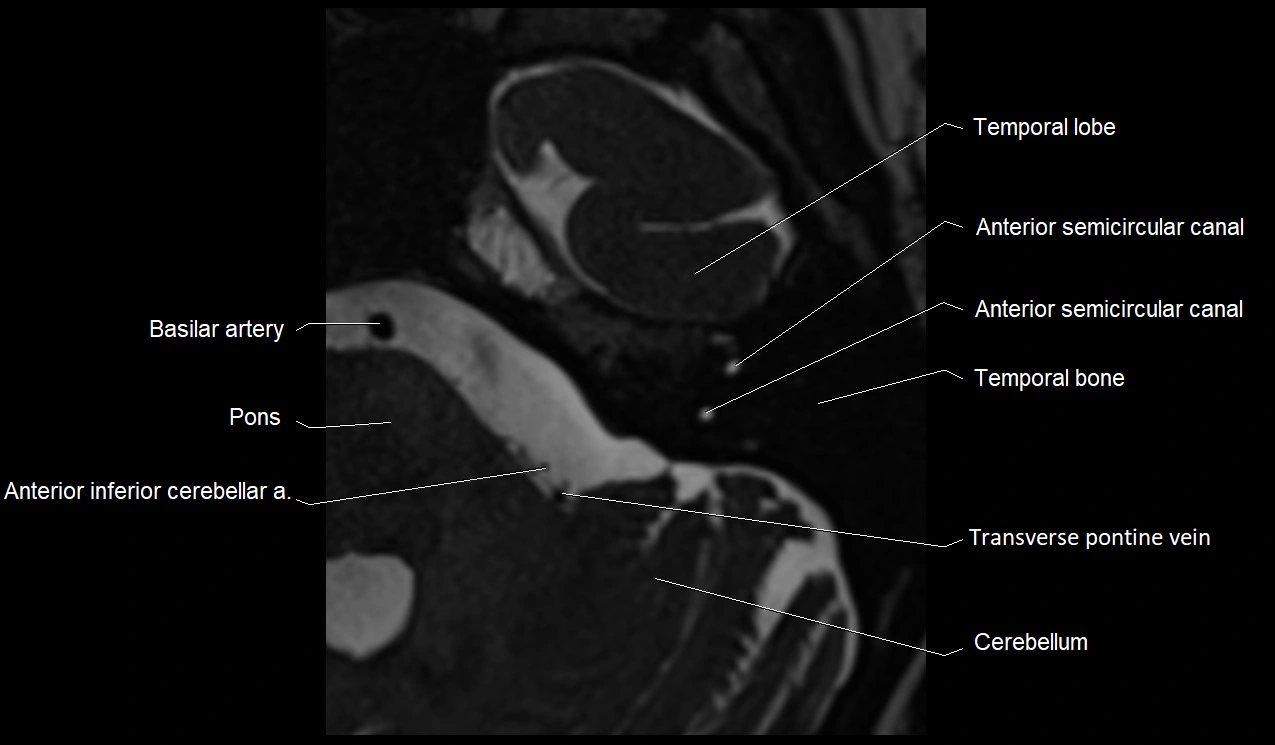

MRI Appearance

• The abducens nerve is a small, thin, linear structure

• Best visualized on high-resolution T2-weighted 3D MRI sequences (e.g., FIESTA or CISS)

• Seen as a hypointense (dark) line running from the brainstem at the pontomedullary junction, traversing the prepontine cistern, and entering Dorello’s canal under the petrosphenoidal ligament, then into the cavernous sinus, and finally the orbit

• May be challenging to visualize in standard MRI due to its small size

• Pathology may be inferred by absence, displacement, or enhancement of the nerve